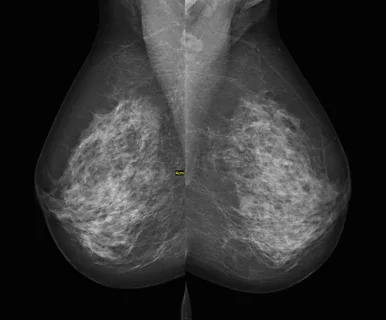

The breast imaging market involves diagnostic imaging technologies that are used for early detection and diagnosis of breast cancer. Mammography has been the gold standard for breast cancer screening and comprises X-ray examinations conducted to detect early signs of breast abnormalities. Other modalities such as breast ultrasound and breast MRI aid in screening and examining the breast tissues in greater depth.

Breast imaging market trends include growing adoption of digital breast tomosynthesis also known as 3D mammography. 3D mammography creates a 3D image of the breast and has demonstrated superior detection of invasive breast cancers compared to digital mammography. Another key trend is an increasing focus on developing AI and machine learning algorithms for breast cancer screening and interpretation of scans.